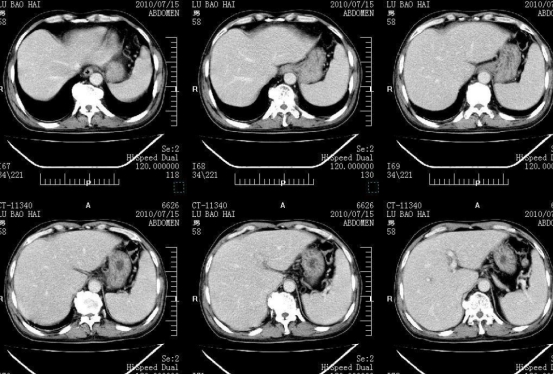

5、定期检查。定期检查是预防脑梗最好的手段之一,通过检查可以及早发现大脑是否已发生病变,另外也可提前知晓个人身体状况,防止相关疾病发生。

检查的项目包括尿常规、血常规、血压血糖、肝肾功能、心电图和CT等等,其中检查前一定要空腹状态进行,千万不要吃任何食物以免影响最终结果的准确性。